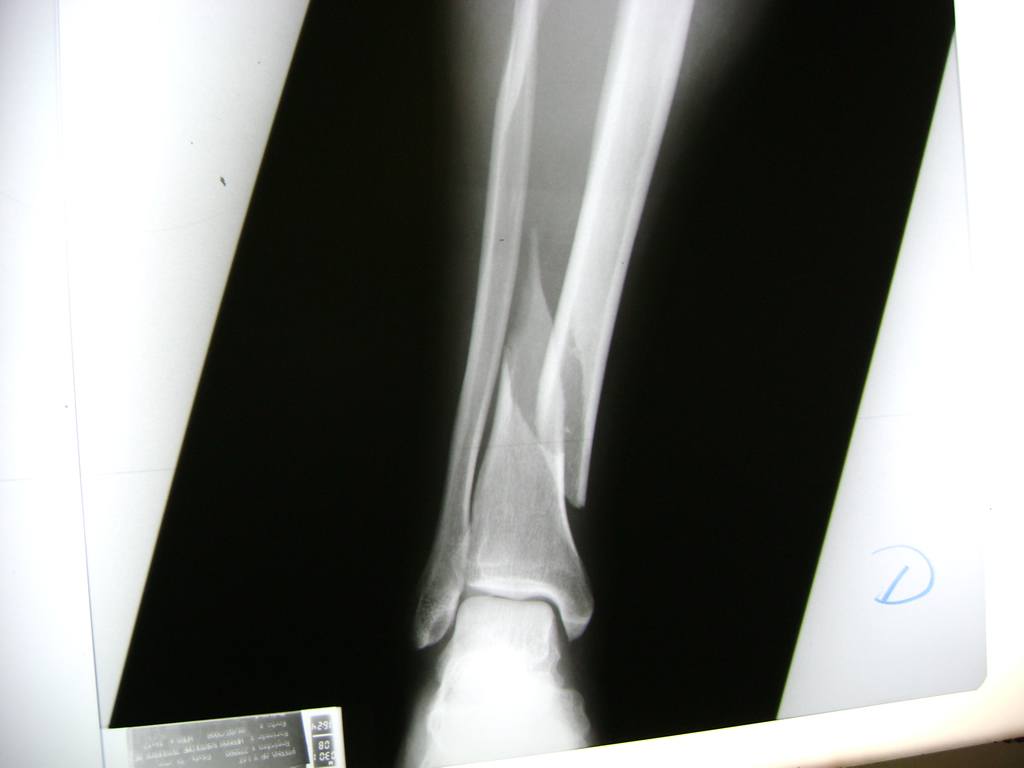

Cirugías de Tobillos

Aunque cada uno de estos huesos puede fracturarse por separado, normalmente la rotura es una lesión que se produce de forma conjunta

La mayor parte de las roturas implican a la parte proximal del hueso (parte del hueso próximo a la rodilla) o a la parte distal (parte del hueso cerca del tobillo).

Debido a la fina cobertura de piel que recubre la tibia y el peroné, las fracturas generalmente son abiertas, es decir, el hueso roto rasga la piel, atravesándola. Las fracturas de tibia y peroné generalmente se producen por un fuerte impacto o torsión.